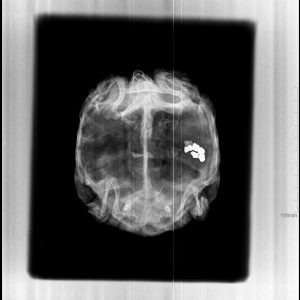

El diagnóstico por imagen es una herramienta fundamental en la medicina veterinaria moderna, ya que permite evaluar de forma precisa y no invasiva las estructuras internas del paciente. A través de técnicas avanzadas como la radiografía digital y la ecografía, es posible identificar alteraciones anatómicas y funcionales que facilitan un diagnóstico temprano y un manejo clínico más eficaz.

Nuestro servicio en Mastervet está orientado a ofrecer estudios de alta calidad, con equipos actualizados y protocolos adaptados a cada caso. Realizamos evaluaciones completas que incluyen la interpretación detallada de las imágenes y la emisión de informes clínicos claros, contribuyendo a la toma de decisiones terapéuticas.

Trabajamos en estrecha colaboración con veterinarios clínicos para asegurar una correcta correlación entre los hallazgos de imagen y la situación clínica del paciente, optimizando así el abordaje diagnóstico y el seguimiento evolutivo.